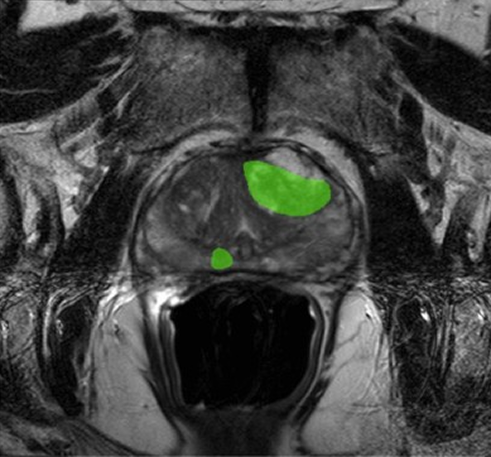

Complex MRI images contain vast information, but without expert labeling and segmentation, even the most advanced algorithms cannot learn effectively. Pareidolia Systems LLP, our annotation specialists combine medical expertise and advanced tools to deliver pixel-level accuracy in marking cancerous and non-cancerous regions. These annotations enable AI models to:

Segmentation and 3D Modeling: A New Dimension to Cancer Analysis

Traditional 2D medical imaging has its limits. With precise segmentation and 3D modeling, prostate cancer visualization becomes far more comprehensive. At Pareidolia, our advanced segmentation techniques allow for precise mapping of tumor boundaries, while our 3D modeling process converts these segmentations into realistic anatomical structures.

These 3D models assist AI algorithms and clinicians alike in:

- Understanding tumor morphology and spread.